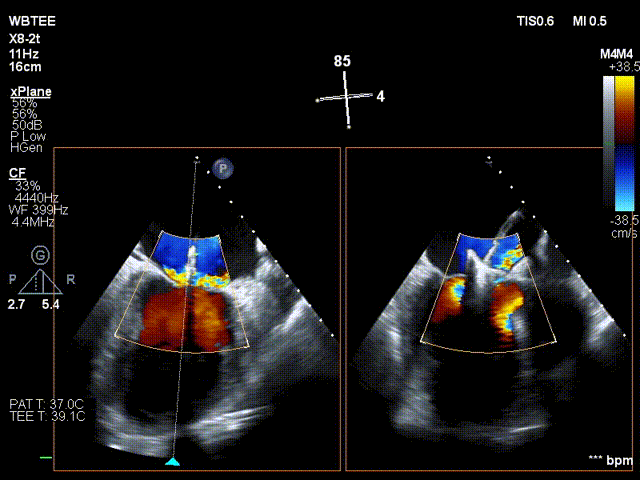

在食道超声王蓓主任的紧密配合下,经食道超声引导后傅国胜教授使用二尖瓣夹准确成功捕获前叶A2和后叶P2反流最严重区域,并予夹合,使二尖瓣在收缩期由大的单孔变成小的双孔,显著减少了二尖瓣反流。

捕捞瓣叶

夹持瓣叶并关紧夹臂

反复测试二尖瓣钳夹的稳定性,超声复查提示二尖瓣夹内侧反流有效改善,外侧仍有部分反流,平均跨瓣压差2mmHg,肺静脉收缩期逆流频谱恢复正向,傅国胜教授团队与超声影像团队充分沟通讨论,计划在二尖瓣夹外侧再置入第二枚二尖瓣夹,遂精准释放第一个二尖瓣夹。

傅国胜教授继续在食道超声影像引导下进行高难度操作,在第一个二尖瓣夹外侧再置入第二枚二尖瓣夹NTR。

再次反复测试第二枚二尖瓣钳夹的稳定性,超声复查提示二尖瓣反流明显改善,平均跨瓣压差4mmHg。